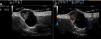

Cutaneous ultrasound (12-18MHz) revealed an oval, well-defined dermal-hypodermal structure measuring 1.85×1.23cm. This lesion was cystic in appearance, with an anechoic interior and posterior enhancement. A triangular hyperechogenic area protruding through the wall was clearly visible in the upper pole (Fig. 2A). Color Doppler mode revealed increased peripheral vascularization, especially in the triangular solid portion (Fig. 2B).

Few publications report ultrasound findings for NH, although these findings are similar in all of the reports.2–7 In ultrasound terms, NH is defined as a well-demarcated, oval, dermal-hypodermal cystic lesion that has an anechoic or hypoechoic interior. In 7 of the 8 cases reported, the interior of the lesion contains a solid triangular hyperechoic area that protrudes from the wall of the lesion and that usually shows increased vascularization on Doppler.2–7 These ultrasound findings are associated with the solid cystic areas observed in histopathology. Hyperechogenic foci compatible with calcifications can sometimes be observed.4